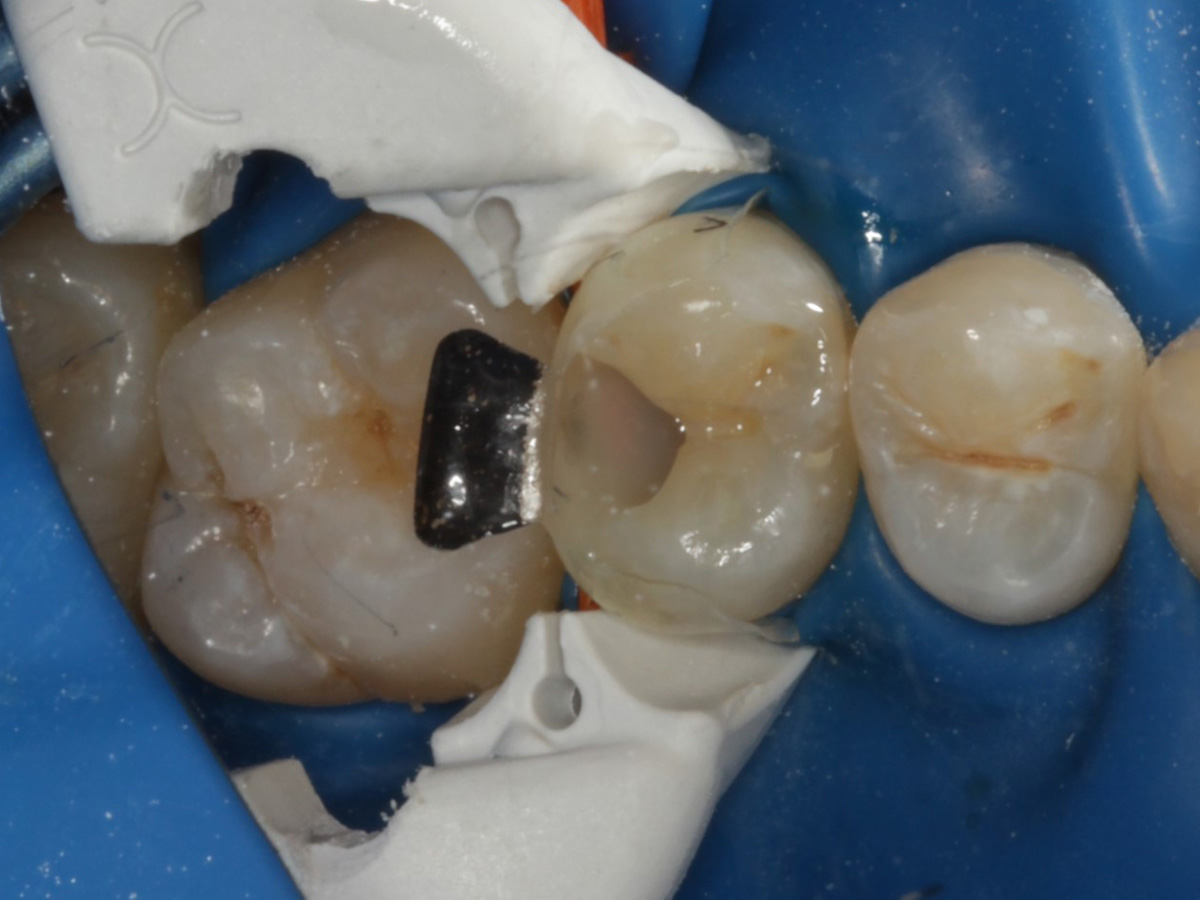

Abbildung 4

Schutz des Nachbarzahnes und des Kofferdams mit wiederverwandter Bioclear Biofit Matrize (gereinigt und sterilisiert); Separation zur Applikation der Matrize mit Heidemannspatel